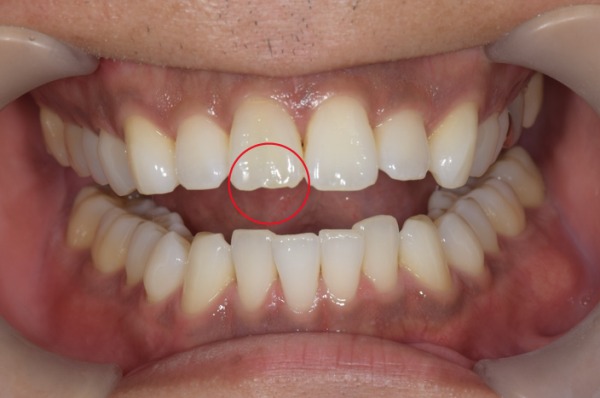

開口時の写真です。

診査したところ過去に治療された右上前歯の先端がわずかに欠けていました。

同部位は過去に神経の治療を行っていました。